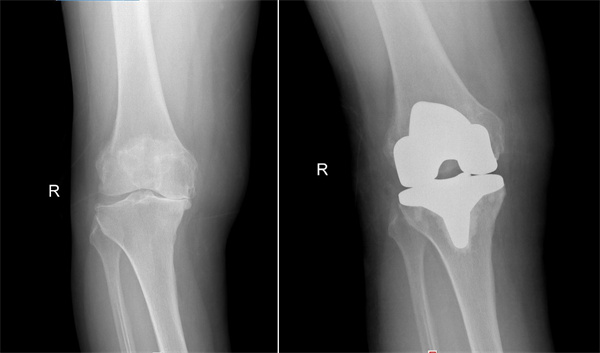

右膝术前术后对比

2022年10月,张阿姨在湖南省第二人民医院骨关节运动医学科诊断为双膝重度骨性关节炎,并接受右膝关节置换手术。出院后主治医生积极微信与患者保持联系,指导康复训练,定期复查,右膝关节功能恢复良好,也不痛了。但是左膝关节问题同样明显,跛行严重,为进一步提高生活质量,解决疼痛问题,2025年9月,张阿姨再次来到湖南省第二人民医院骨关节运动医学科,于近日顺利接受左膝关节置换。术后第一天,即可在助行器辅助下下地行走。目前,张阿姨正在进一步康复中。